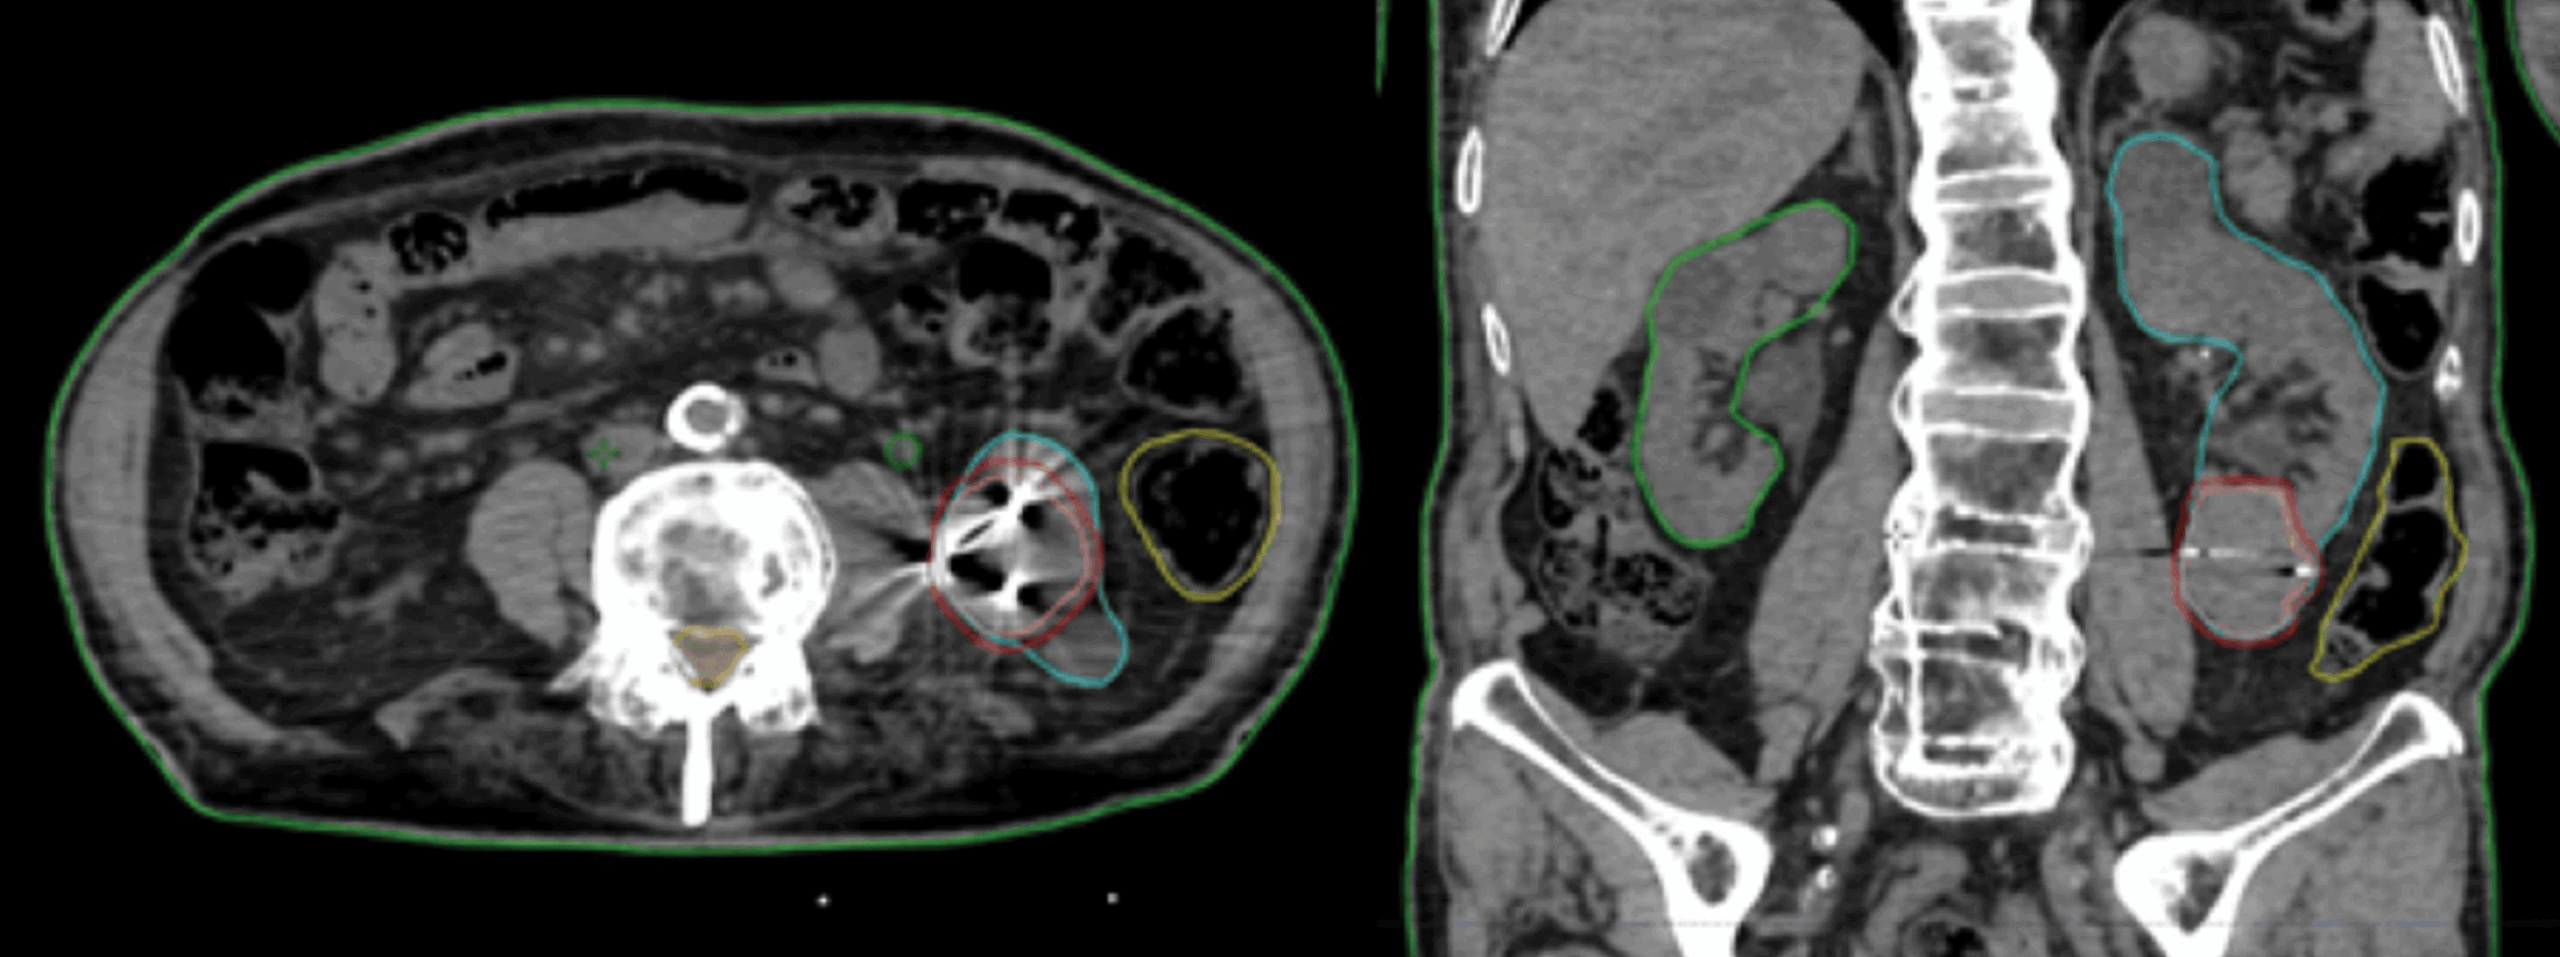

This retrospective study examines cancer control and health-related quality of life (HRQOL) outcomes in high-risk prostate cancer patients receiving robotic stereotactic body radiation therapy (SBRT) with Synchrony® real-time adaptive motion management.